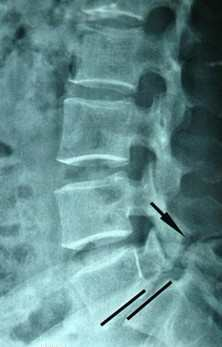

腰椎滑脱指腰椎椎体相对于其邻近的椎体产生了移位。成年人腰椎滑脱的发病率为3%~4%,男女间的比例为2:1,女性严重滑脱多见。6岁以下儿童很少发生此病,20岁左右的青年人,易发生腰椎滑脱。主要原因包括先天发育不良、椎板岬部断裂、退行性病变、外伤等。主要症状是腰背痛,过度活动、体育运动后加重,有时也可伴坐骨神经痛。卧床休息、牵引及支具保护,可有效缓解症状。保守疗法无效时,可施行手术治疗。严重者可发生椎管狭窄、马尾及神经根受压,出现跛行。经治疗大多数患者预后良好,症状可缓解。